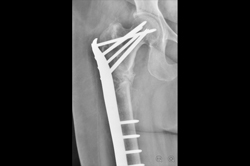

Intertrochanteric Fracture